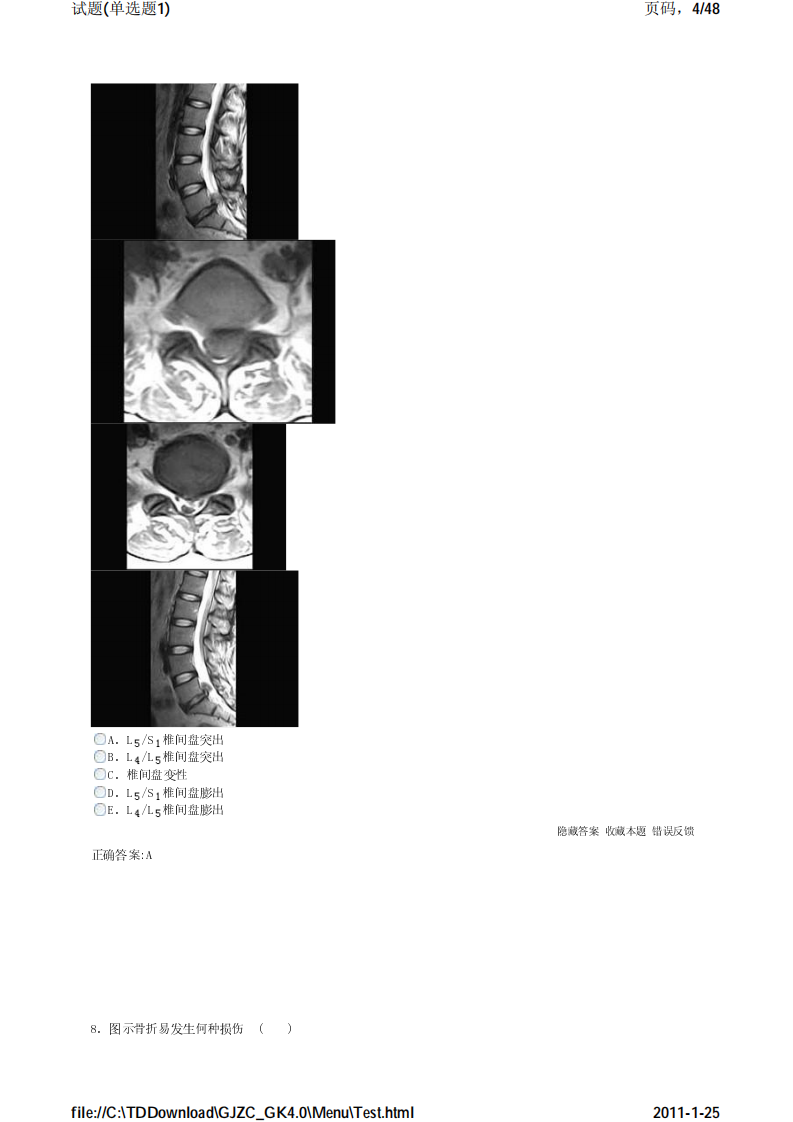

考试宝典 医学高级职称考试 骨科 单选题1.pdf

骨科